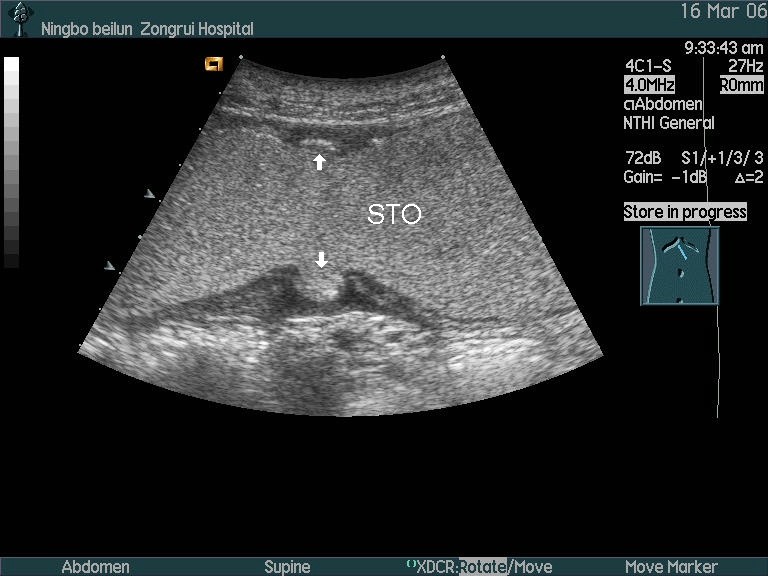

超声检查胃癌的影像图

内异物伴胃窦部胃壁增厚:胃超声检查已经被写入胃癌诊疗规范(2018版)

图片尺寸768x576